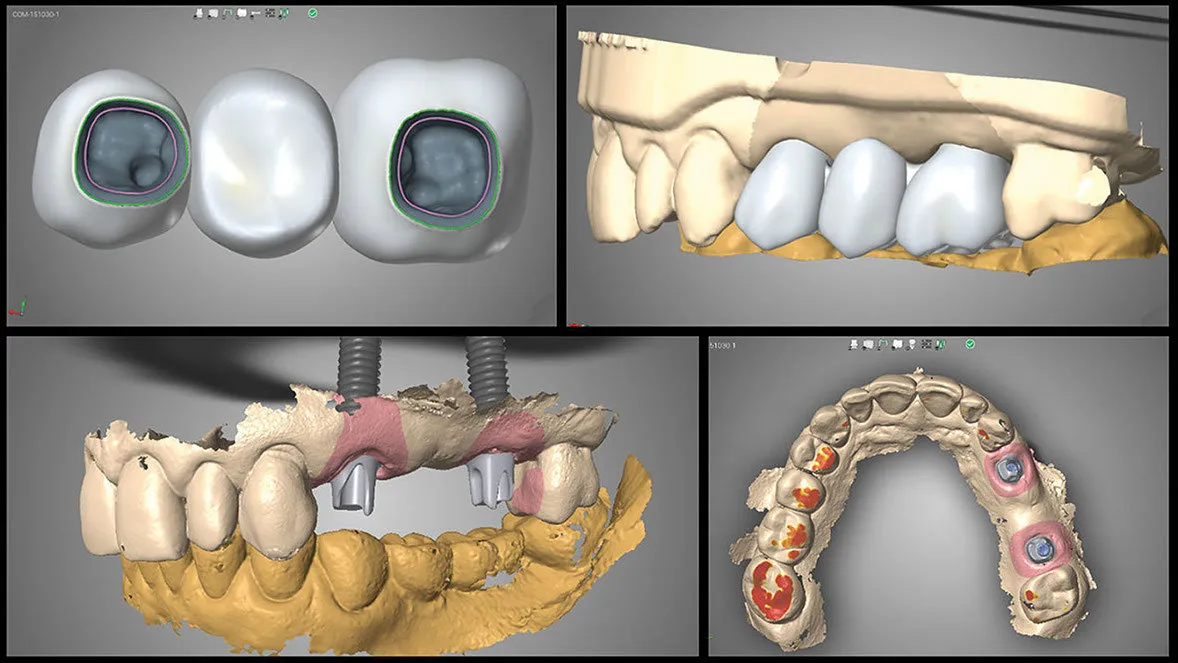

We use digital innovations to digitally plan implant placement to receive the most predictable outcome through:

• Create radiographic and surgical templates from guided surgery software

• Nerve detection, segmentation, and implant placement for prosthetic-driven implant planning with guided surgery software.

• Precision surgical guided placement using restorative-driven three-dimensional imaging and planning allows for more predictable surgical placement.

• High surface digital impression scanning and CAD/ CAM milling allows for precision design and modeling for improved accuracy of both the abutment and restorations. Combining these digital technologies allows us to plan and treat the patient in a more efficient manner with more predictable results.

Digital Implant Dentistry in Burnaby BC, IMPrESS Perio Implant Center